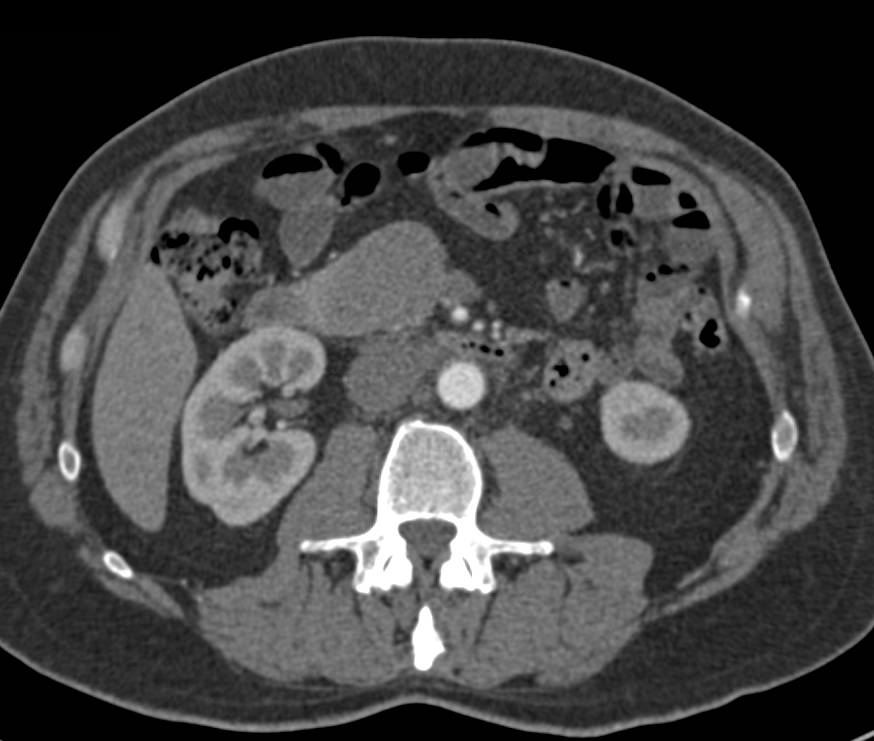

Incidental Pulmonary Embolism (PE) in the Pulmonary Artery to Right Lower Lung in a Patient with Metastatic Pancreatic Cancer